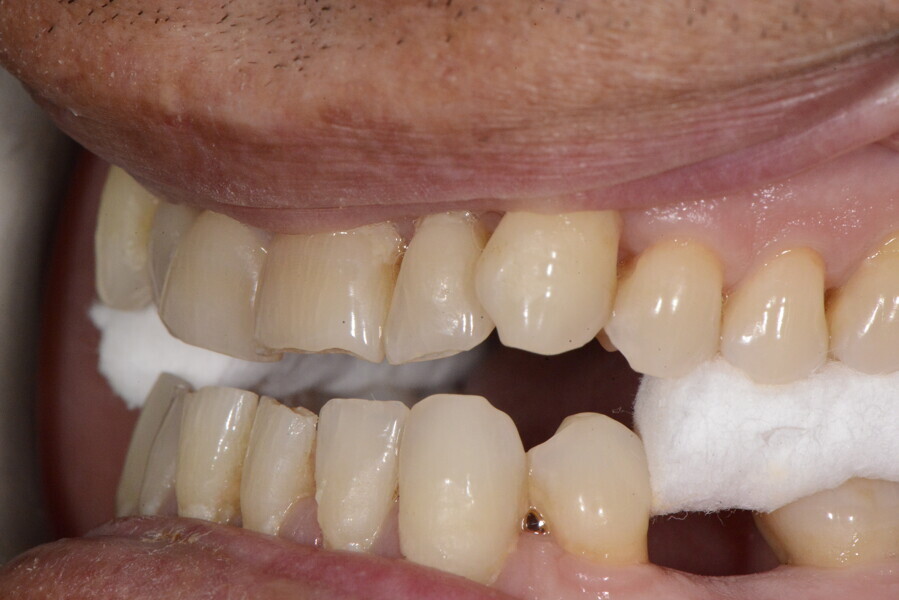

During the first visit, we checked the centric relation with cotton rolls, eliminating the posterior mesialising precontact and then performed a direct composite aesthetic and functional mock-up in this new position, not only to motivate the patient regarding the final result but also to help him understand better overall why tongue therapy, tooth alignment and dental resurfacing for augmentation of the vertical dimension of occlusion were required (Figs. 14 & 15).

After the first phase of aligner treatment, we had achieved better inter-arch coherence, better maxillary arch expansion, and some space for improving the anterior tooth proportions restoratively (Fig. 19). We then temporarily restored the anterior teeth directly with composite, closing the spaces, improving the tooth proportions and further increasing the maxillary arch expansion (Fig. 20). We used restorative arch expansion to reduce the orthodontic destabilisation of the teeth to achieve the correct inter-arch coherence and retain the teeth in the cortical bone.38 A refinement aligner phase was undertaken to improve the final alignment of the gingival zenith and to improve the inter-arch coherence (Fig. 21). The periods of the first orthodontic phase and of the refinement were used to augment the mandibular and maxillary bone and to place the implants (Fig. 22). At the end of the orthodontic treatment, the case was finalised with ceramic veneers in the anterior area and temporary restorations on the implants in the posterior area (Figs. 23–26).